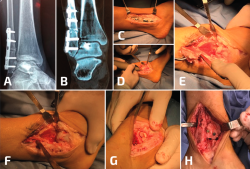

Figura 3. En este paciente, además de la pseudoartrosis del peroné, se asocia un gran defecto osteocondral del astrágalo (A, B, C). Para acceder a la lesión, se realizó una osteotomía en la región lateral de la tibia (D, E, F). Después de la colocación de los injertos tomados de la rodilla, se realizó la osteosíntesis de la osteotomía de la tibia y posteriormente se trató la pseudoartrosis del peroné (G, H).

Figura 7. En este caso, además de una deformidad en valgo del plafón, se agrega una pseudoartrosis del peroné con acortamiento del mismo y un ensanchamiento de la sindesmosis. Solo se ve la mitad lateral del plafón impactada en valgo, por lo que una osteotomía en cuña de cierre con base medial de la tibia no es necesaria (A, B). Se desbrida la sindesmosis y se retrae el peroné hacia lateral (C), se elonga y se realiza una osteotomía intraarticular (plafonplastia) del borde lateral de la tibia (descrita por Myerson) (D). La tibia lateral se distrae gradualmente hasta observar la posición neutra del pilón (E); se coloca injerto óseo y se estabiliza la sindesmosis (F).

Figura 8. Generalmente, las deformidades en valgo del plafón tibial se acompañan con deformidades severas del peroné; sin embargo, a veces pueden ser consecuencia de una fractura de Weber B (A, B). En este caso, la gotera interna se limpió por artroscopia, se elongó el peroné, pero todavía hacía falta una osteotomía de cierre de base medial (C).